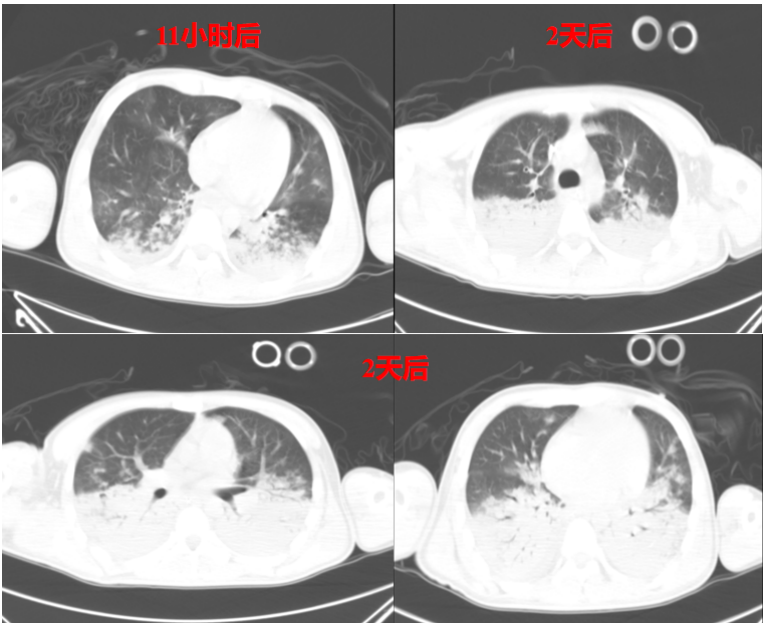

实际案例中,我们看到这一例ARDS患者,早期呈病毒性肺炎的磨玻璃样改变(图7),随着病情进展,11小时后氧合下降,胸部CT可见渗出增加、肺实变,予以气管插管,呼吸机辅助(图8);呼吸机支持2天后,胸部CT示实变进一步加重,呈现ARDS典型的“重力依赖”CT表现(图8)。这种情况可能就是呼吸机参数设置不当,加重了肺损伤。

图片

图8  11小时后和2天后胸部CT